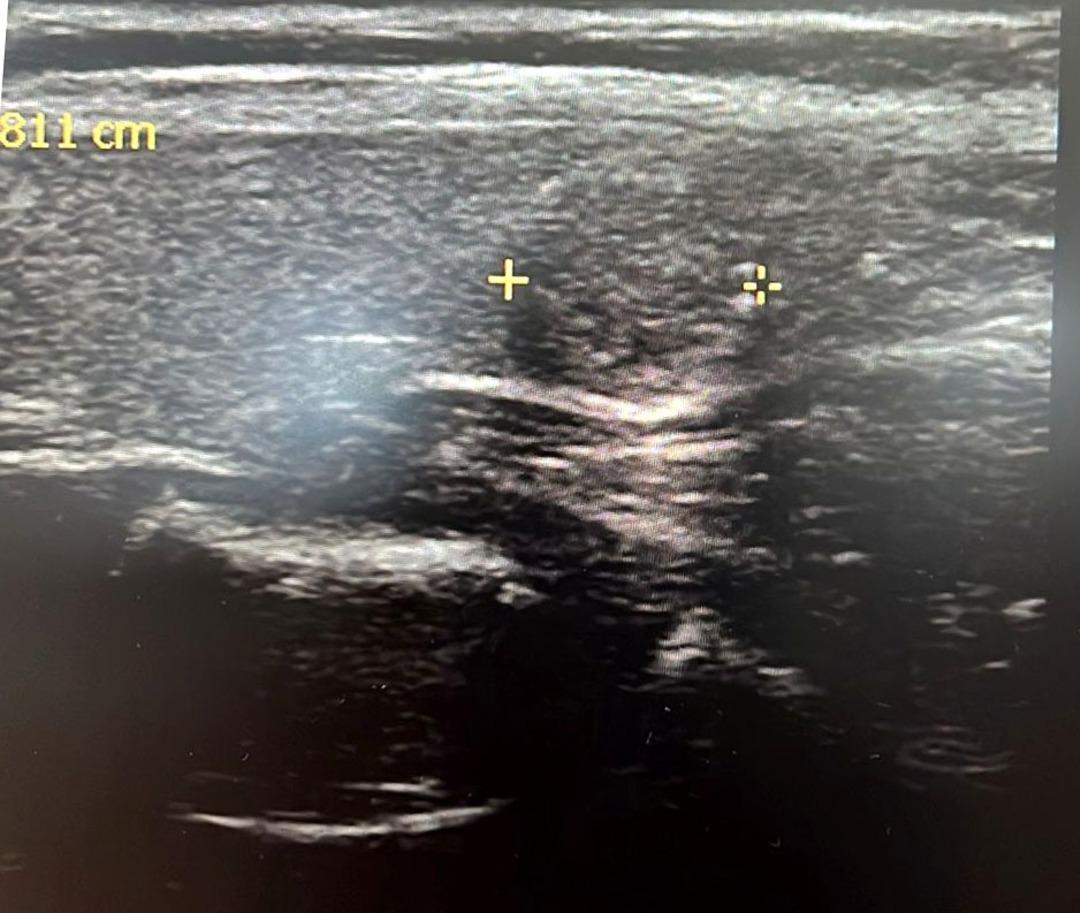

Tiroit nodülü tespitinde farkındalığın artığını ifade eden Dr. Demir, "Nodül tespitindeki farkındalığımız arttı. Tiroit ultrasonu kullanıyor olmamız da bu artışa etken oldu. 'Bası bulgusu' ile dokunarak muayene ettiğimizde; mevcut olan nodüllerin yaklaşık yüzde 20’sini tespit edebiliyoruz. Nodüllerin birçoğunun özelliklerini ve boyutlarını ise tiroit ultrasonu ile tespit ediyoruz. Son dönemlerde vakalarda artış var. Bazen hiçbir semptomu olmayan hastalarda da tiroit nodülleri tespit ediyoruz. Nodülleri özelliklerine göre değerlendirerek gerekli hastalardan biyopsi alıyoruz. İyi ya kötü huylu nodüle göre tedavi uyguluyoruz. Nodülü belli aralıklarla takip ediyoruz. Tiroit nodüllerinin yüzde 10 ila 20 kadarı kötü huylu olabiliyor. Birçok kanser türü erkek hastalarda fazla görülürken, özellikle tiroit kanseri sıklığı kadın hastalarımızda daha yüksektir. Kadın hastalar daha sık muayeneye geliyor ve farkındalıkları daha yüksek" dedi.